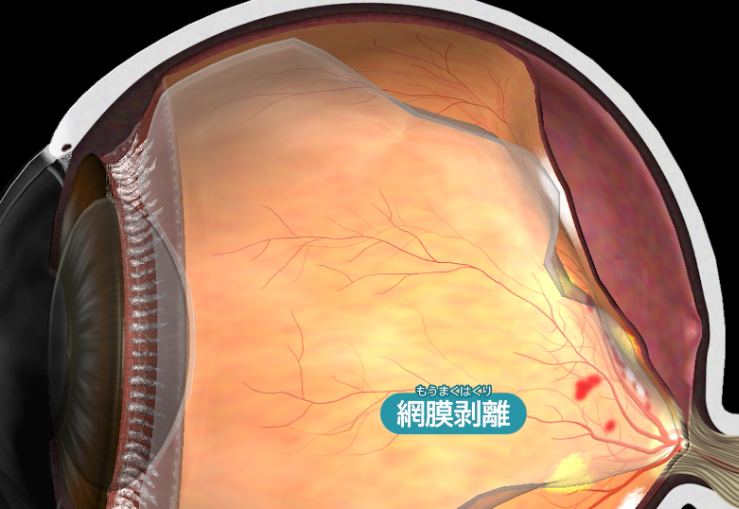

網膜剥離

網膜剥離とは、網膜が眼球壁から離れた状態です。

放置して網膜全体が剥がれると最終的には失明に至ります。

網膜に割れ目・穴が生じている段階に留まるものを「網膜裂孔」、網膜が部分的にでも剥がれているものを「網膜剥離」と区別します。網膜剥離の方が重症であり、剥がれた部分では光を感じにくくなります。

網膜剥離の場合には、視野欠損が生じます。視野の一部が見えなくなります。網膜剥離を放置して、網膜の中心部分(黄斑部)が剥がれると、視力が大幅に低下します。また眼鏡やコンタクトレンズを使っても矯正はできません。症状に気づいた時には、すぐにご相談ください。

網膜剥離の場合には、視野欠損が生じます。視野の一部が見えなくなります。網膜剥離を放置して、網膜の中心部分(黄斑部)が剥がれると、視力が大幅に低下します。また眼鏡やコンタクトレンズを使っても矯正はできません。症状に気づいた時には、すぐにご相談ください。